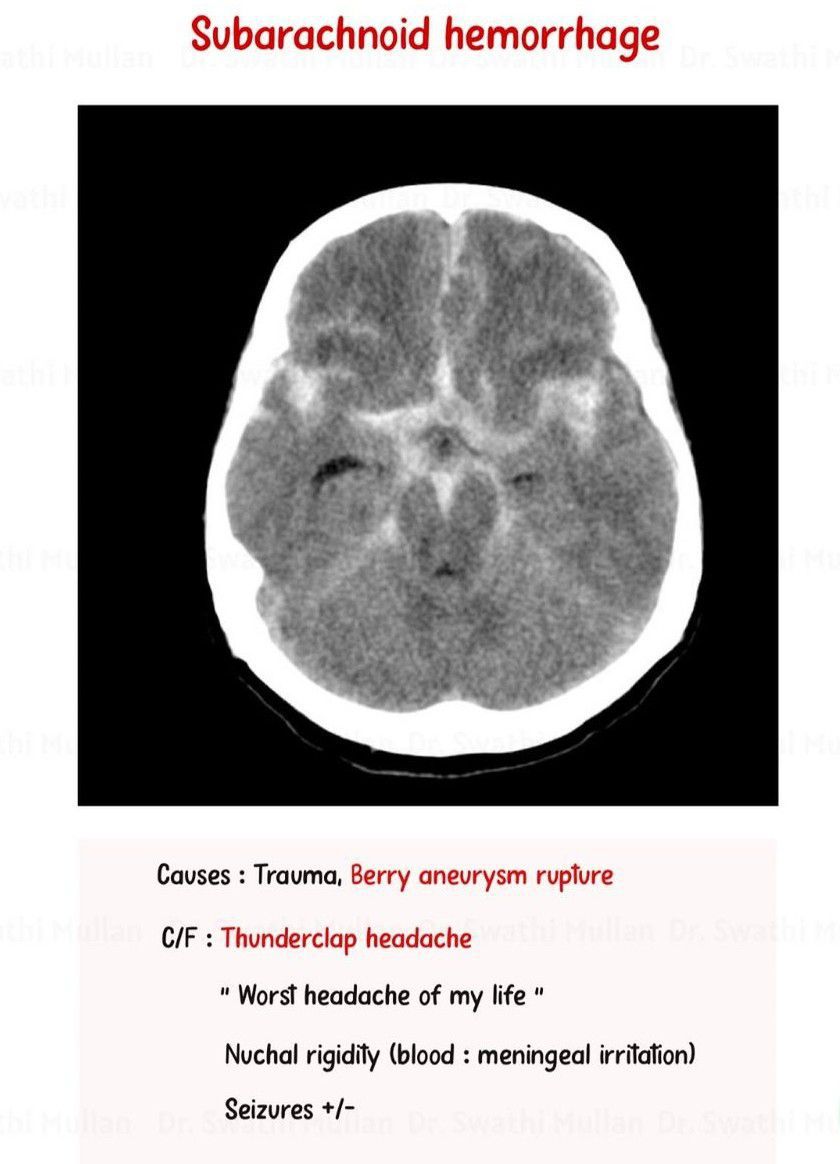

Subarachnoid Hematoma

Here is some important information to review.